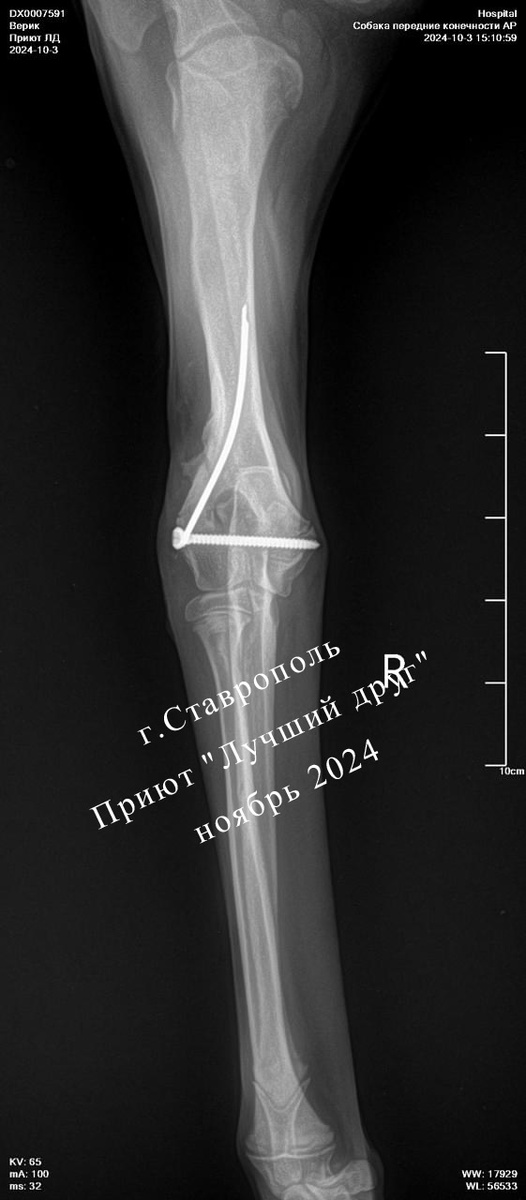

Черного щенка-подростка сбила машина, в шоке он побежал через дорогу, упал в ливневку и застрял в трубе... Очевидцы происшествия хотели достать пса своими силами, но ничего не получилось, достали щенка ребята из МЧС. У него были сломаны две передние лапы, переломы сложные, уму непостижимо, как он с такой невероятной болью вообще смог двигаться. В Ветцентре щенка оставили на стационар стабилизировать состояние перед операцией и потом прооперировали обе лапы сразу.

Потом Верик, так назвали малыша, лечился в приюте, ездил на плановые осмотры и вот, наконец-то ему сняли скобы и серкляжи. Верик поправился, очень этому рад и ищет дом!